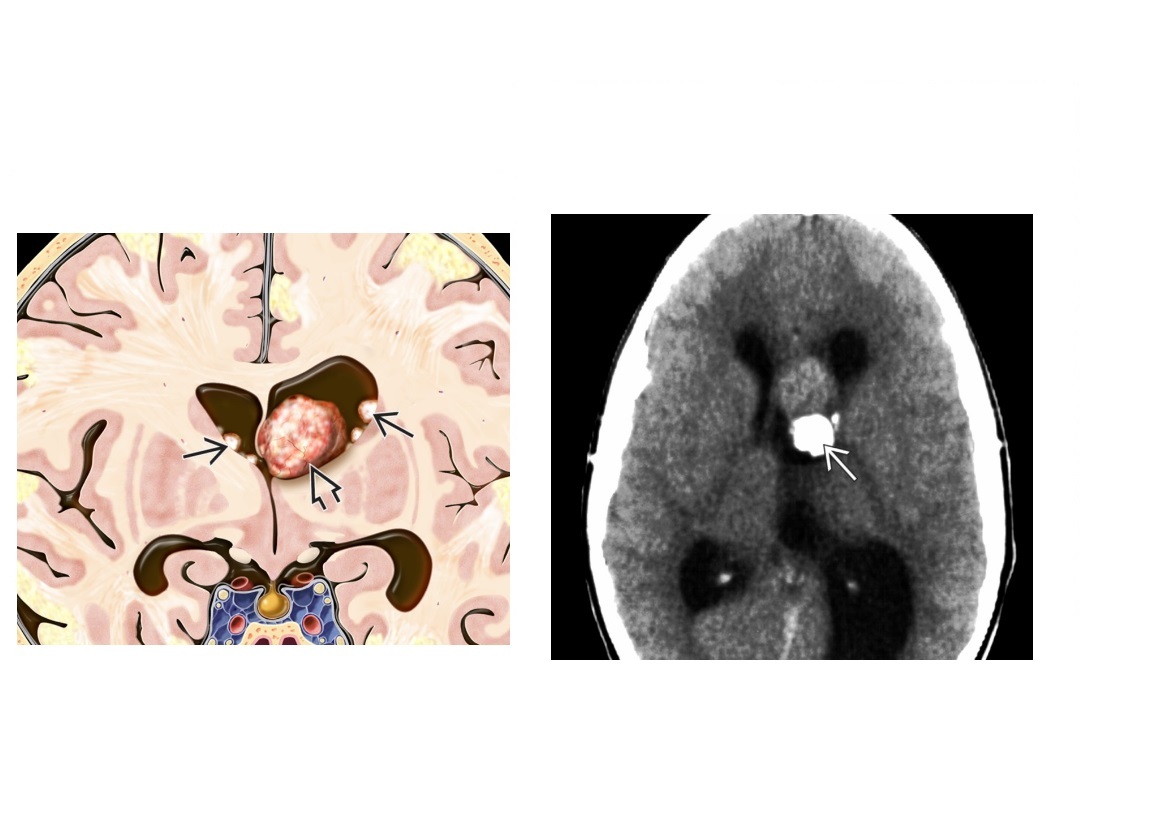

What brain tumour is found in Tuberous Sclerosis?

A

Subependymal giant cell astrocytoma (SEGA)

aka Intraventricular astrocytoma of tuberous sclerosis complex (TSC

Enlarging, enhancing foramen of Monro mass in patient with TSC

Tuberous sclerosis is triad of

-facial angiofibromas

-seizures

-mental retardation

Cortical/subcortical TUBERS

- expand overlying gyri, low on CT,

- can have cystic and Ca2+ transformation.

DDX - TORCH namely toxo and CMV can cause periventricular Ca2+